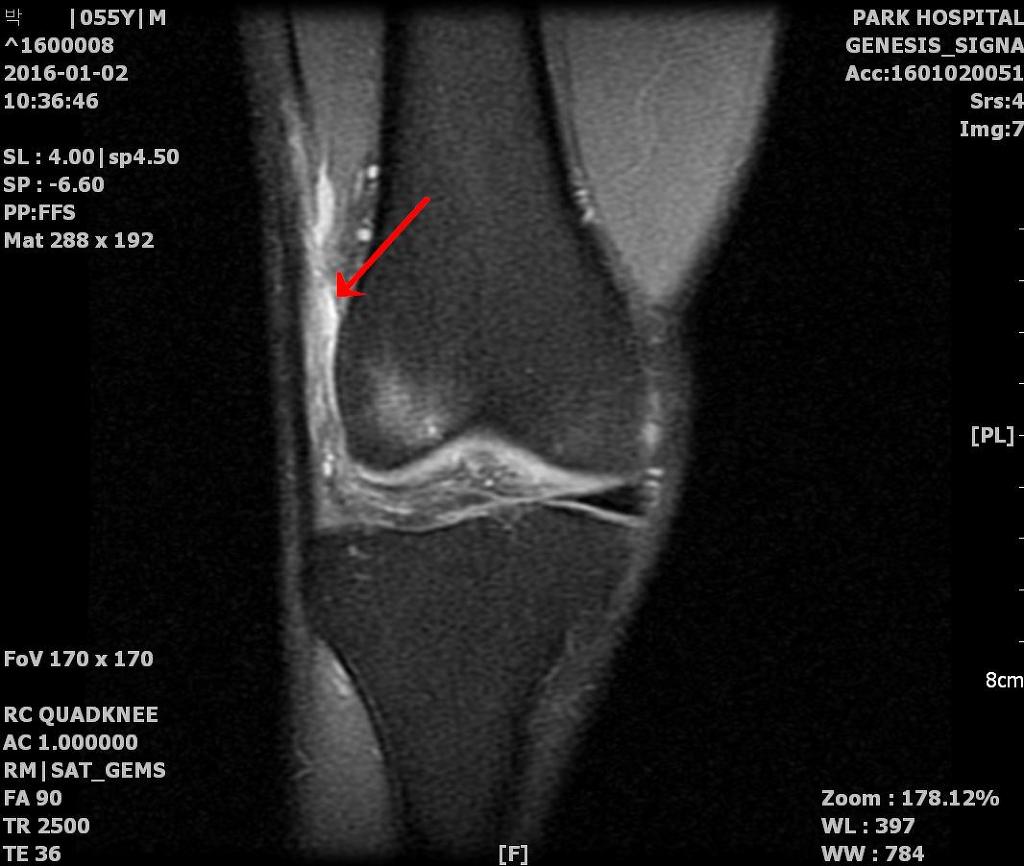

장경대 증후군, 장경인대증후군, ITBS

주로 구부리고 펼 때 마찰이 생겨 통증을 일으키는 장경인대증후군

원인은 반복되는 슬관절의 굴곡 및 신전시 외측 대퇴 상외과부위로 장경대(ITB)의 마찰으로 유발됩니다.